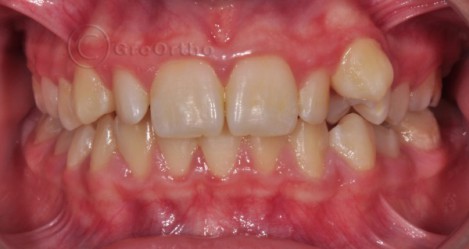

Двустранно дистализиране на молари

Дистализирането на моларите е ортодонтска процедура, която се прави за увеличаване периметъра на зъбната дъга в задните сегменти. Горните молари се придвижват дистално и се коригират клас II съотношенията при моларите. Използва се постигнатото място за подреждане на зъби в средния или фронтален сегмент.